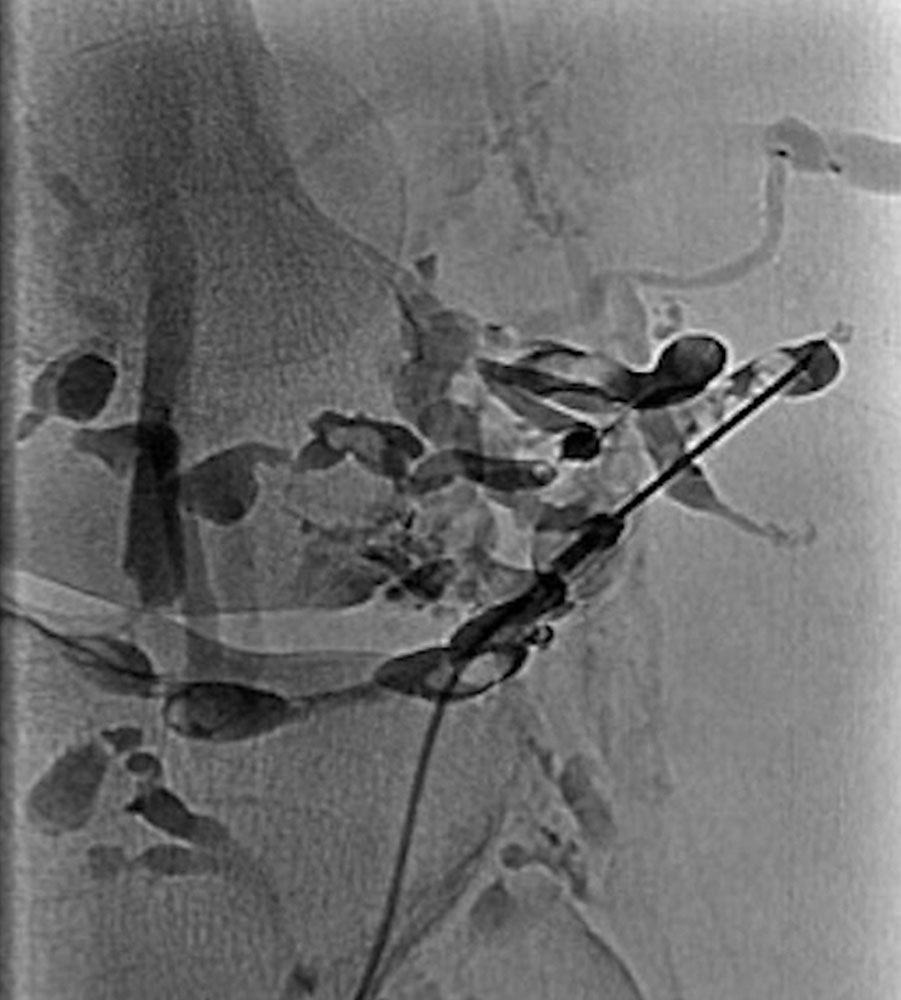

Thrombophlebitis is also depicted in direct phlebography or varicography (in the context of therapy). Intravascular thrombi present themselves as local non-contrasted areas within a vessel. Thrombophlebitis per se is not an indication for phlebography.

It is important to know whether patients with larger venous malformations have venous communications draining to the deep conducting venous system. If these connections are present and have a large lumen, clinically relevant blood clots may drain off from the venous malformation and cause thromboembolism with thrombosis and / or pulmonary embolism. Detection of these connections (from VM to deep venous system) is best accomplished with direct phlebography. If detected, these communicating veins should be occluded.